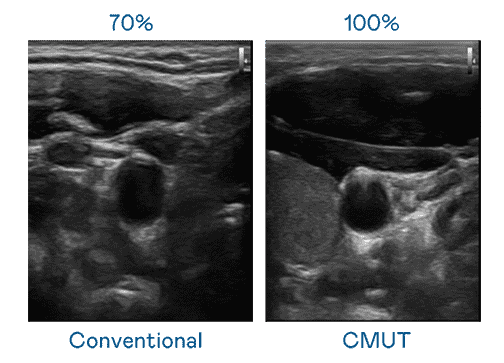

CMUT 技术是一种用电容式微机电元件来产生超音波讯号的技术。。。与传统 PZT 压电式技术相比,,CMUT 频宽增加 30%,,更宽频的超音波讯号让影像解析度大幅提升,,,是实现高影像品质医疗超音波扫描、、、、促进精准医疗发展的关键技术。。。。

大频宽带来超清晰影像

超音波影像的解析度高低,,,,首先取决于探头能发出的讯号频宽。。。欧陆注册 CMUT 可提供高清晰的超音波讯号,,,,提供高频宽、、、、高灵敏度、、、影像纹理细节更高的超音波影像,,,,协助医护人员缩短影像判读时间及利用精准的医疗影像进行诊断。。。